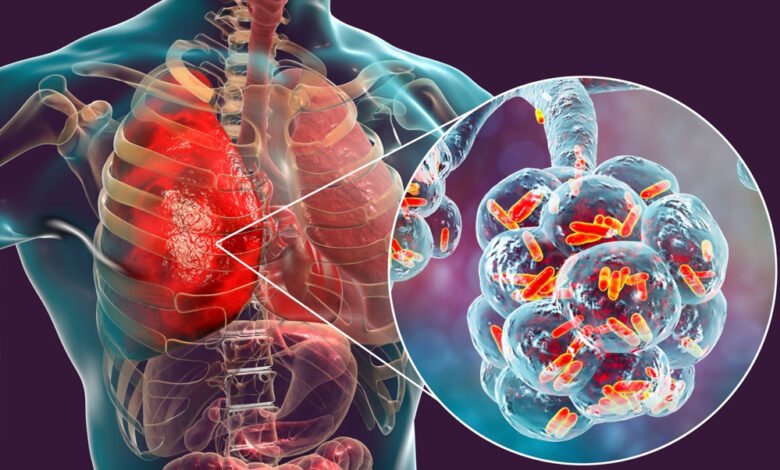

क्या होती है ट्यूबरक्लोसिस?

टीबी रोग माइकोबैक्टीरियम ट्यूबरक्लोसिस कीटाणु के कारण होता है. यह कीटाणु हवा के माध्यम से एक व्यक्ति से दूसरे व्यक्ति में फैलता है. जब सक्रिय टीबी रोग से पीड़ित कोई व्यक्ति खांसता, बोलता है तो टीबी के कीटाणु हवा में फैलते हैं.